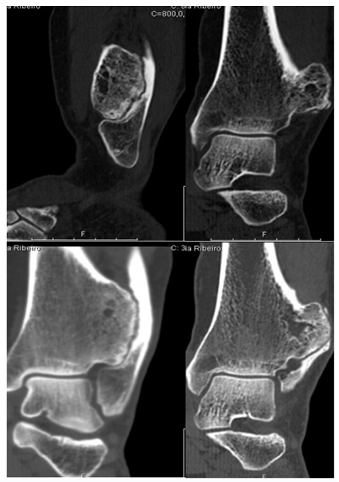

In addition to the X-ray of the left ankle, it was performed Computed tomography (CT) and preoperative Magnetic resonance imaging (MR) for a better definition of the lesion (Figures 2-3).

Figure 2 Preoperative TC, showing the lesion and fibula invasion.